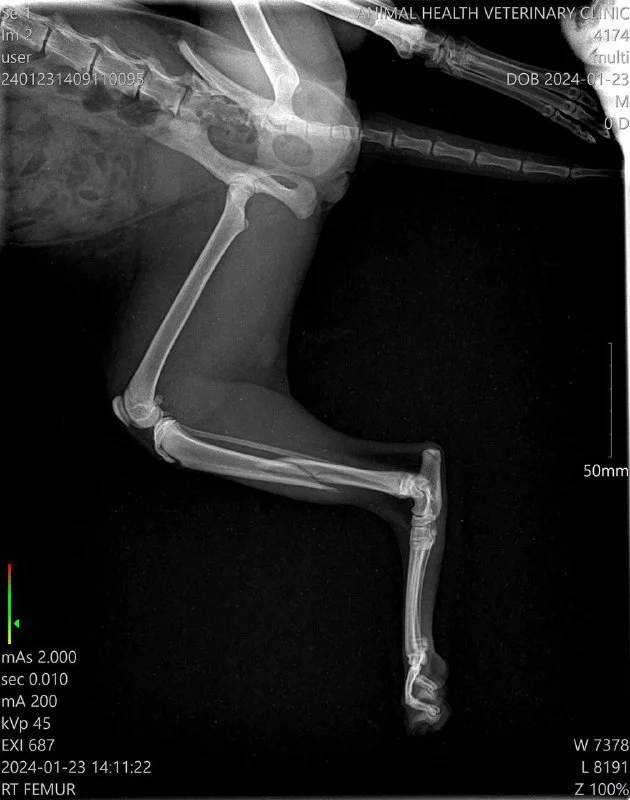

Добрый вечер! На днях увидела кошечку Лисси, которая живет в нашей колонии, она заднюю лапу волочила по земле. Нужно было срочно действовать и соседка Анастасия согласилась отвезти в клинику. Сделали рентген , оказался перелом задней лапки. Вчера была сделана операция , поставили пластины и стерилизовали сразу. Сегодня Лисси выписали. Нужна долгая реабилитация, но самое главное , она в безопасности и под контролем.

Лисси невероятно ласковая и благодарная.

Друзья, если у Вас есть возможность, помогите с оплатой операции. Ей предстоит долгая реабилитация.

Заранее благодарю!

Revolut 96586890

Bank of Cyprus CY46002001950000357027586398

PayPal [email protected]